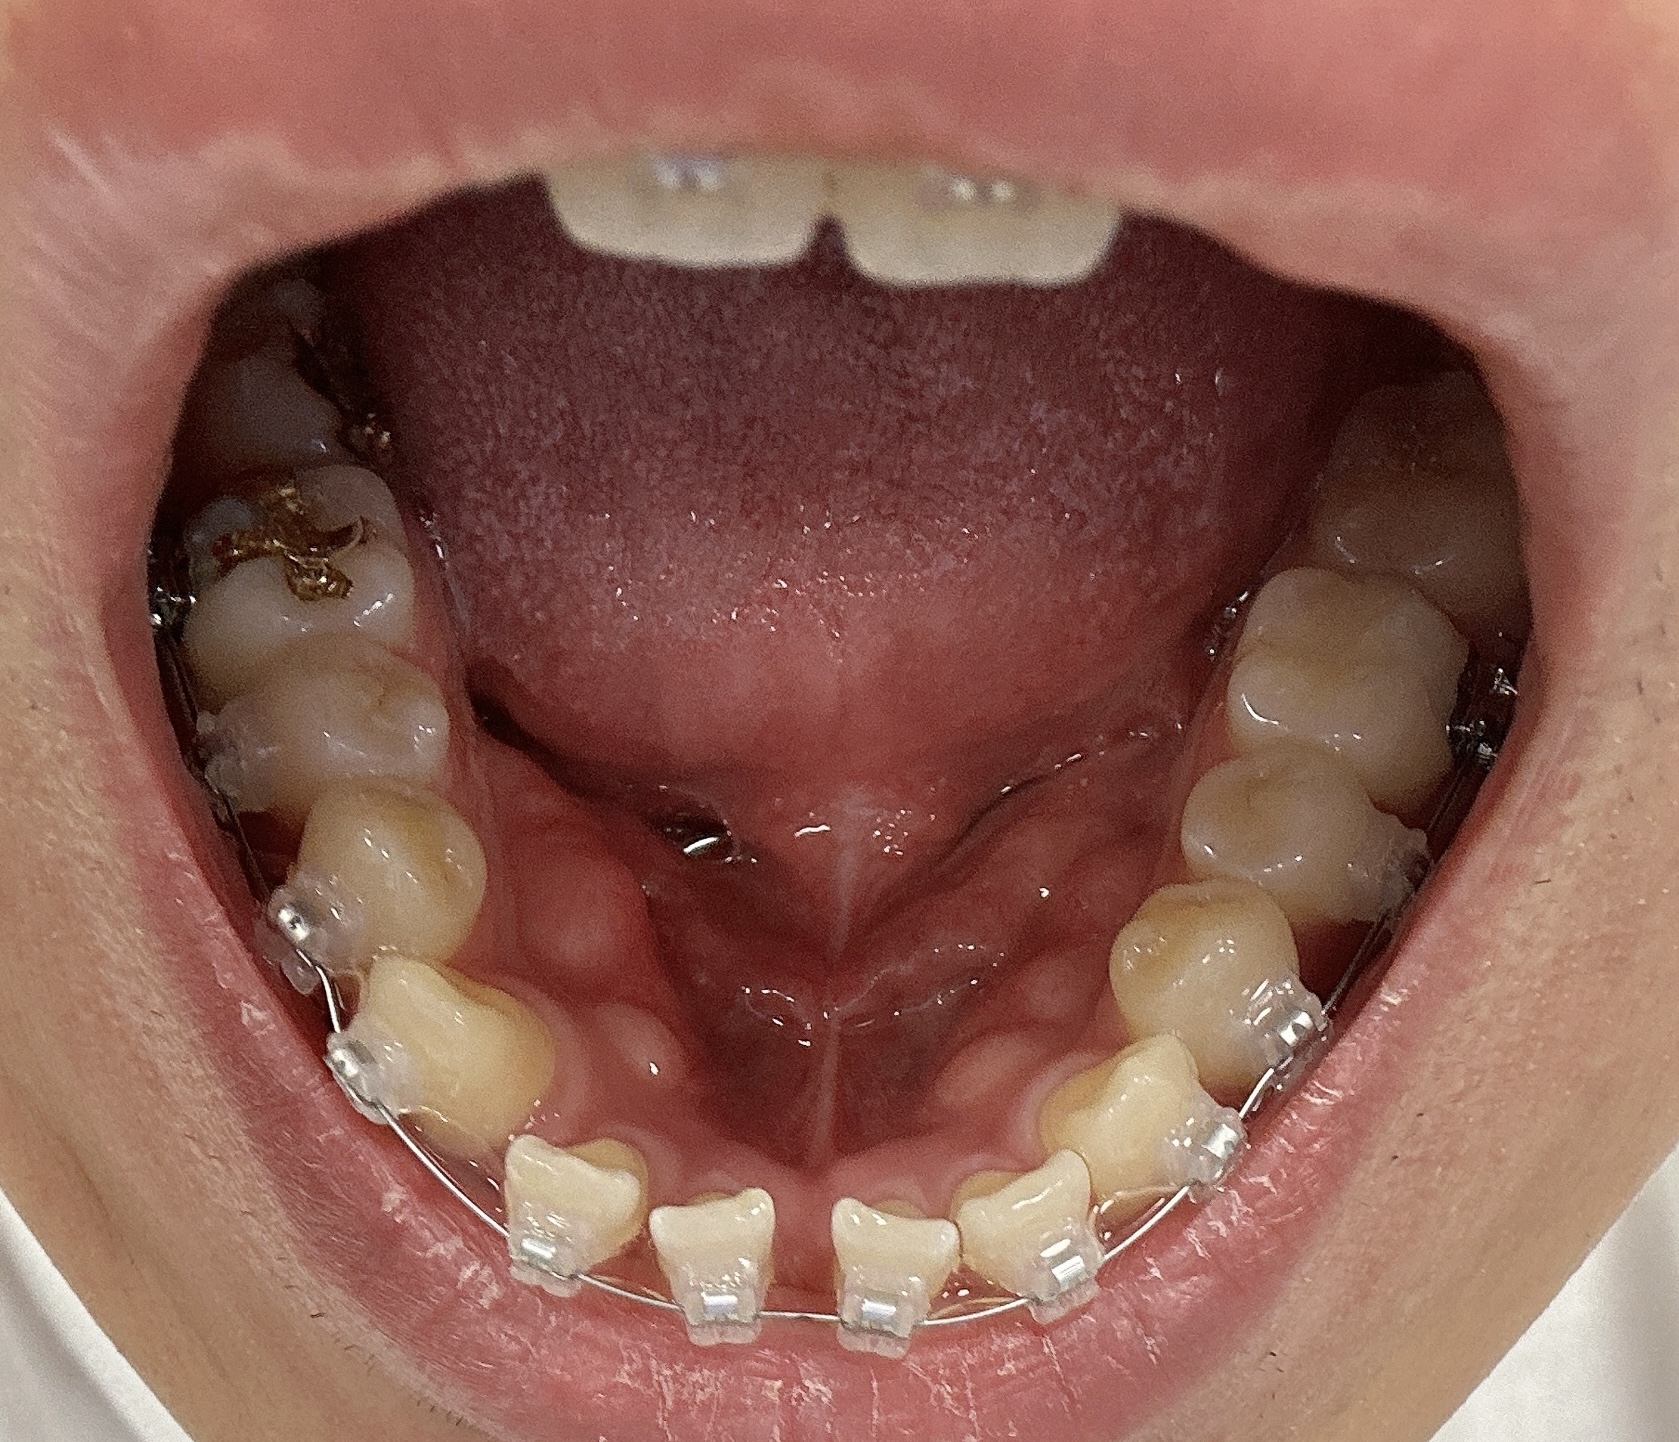

9월2일 교정 1일차

사실 교정기를 장착했을뿐이지 교정이 크게 되거나 한 모습은 없습니다. 당연히 하루 밖에 안됐으니까 그렇겠지만요. 이때만해도 교정이 어떻게 되지? 라고 생각했을때인데요.

교정 시작한지 일주일 정도가 됐을때 입니다. 정확히는 8일 조금 넘은거 같구요. 엄청 크게 느껴지는 모습은 없지만 확실히 앞니가 조금씩 돌아가는 모습을 볼 수 있습니다. 아직까지 엄청 크게 느껴지지는 않지만 앞니가 벌어진 부분이 조금씩 돌아가는것도 느껴지는거 같구요.